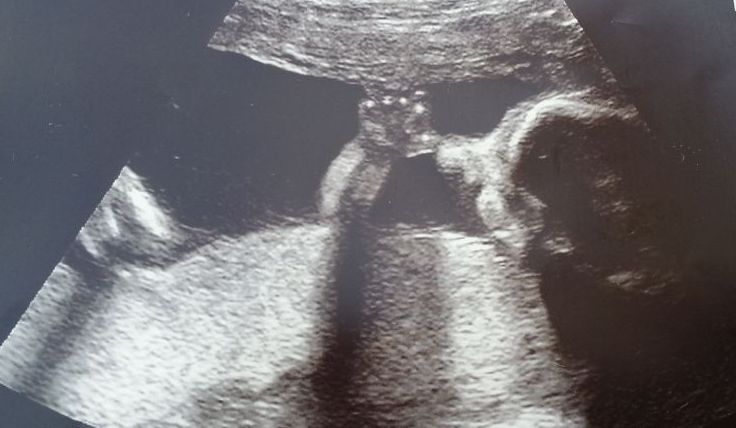

Testy dopadly na jedničku. Vašík na nás vyplazoval jazyk, nechtěl nám ukázat srdíčko a tak jsme si musely dát pauzu a já se musela jít projít, ale nakonec jsme všechno krásně prohlídly a zkontrolovaly a s vědomím, že jsme zdraví, jsme mohli spokojeně odjet domů. A co si o tom myslel náš prcek? To vidíte samy na fotce, měl to těžce na salámu : -)